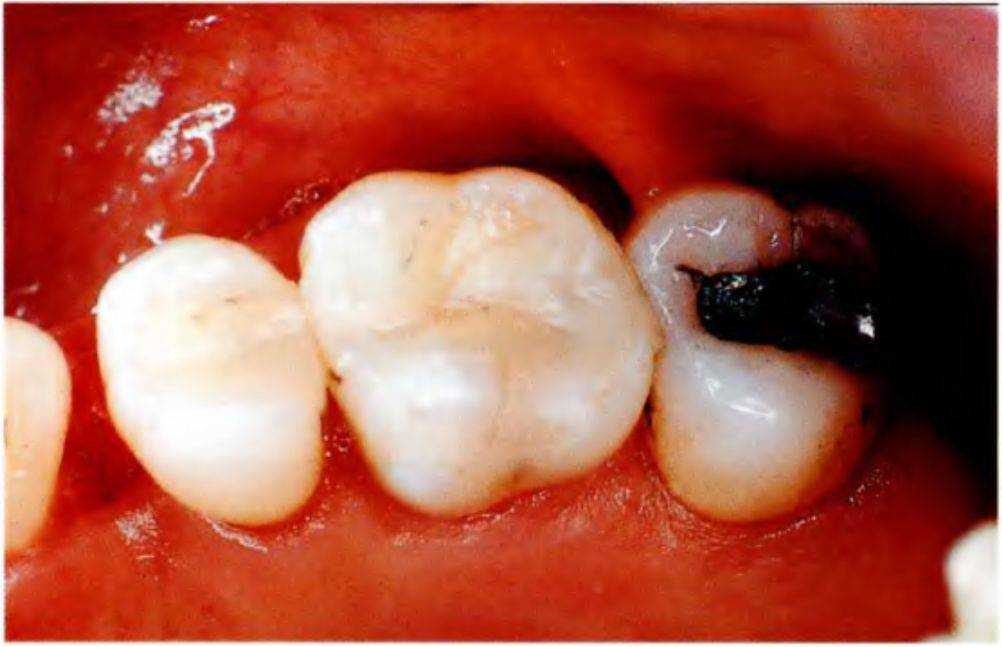

Борозды протравливают фосфорной кислотой в течение 30 с, затем промывают в течение 15 с и тщательно высушивают (рис. 4-2f). Для сохранения просветов в области межзубных пространств вводят смазанные вазелином корды Веджетс (Wedgets) (рис. 4-2 д). При наличии обнаженного дентина используют дентинный адгезив.